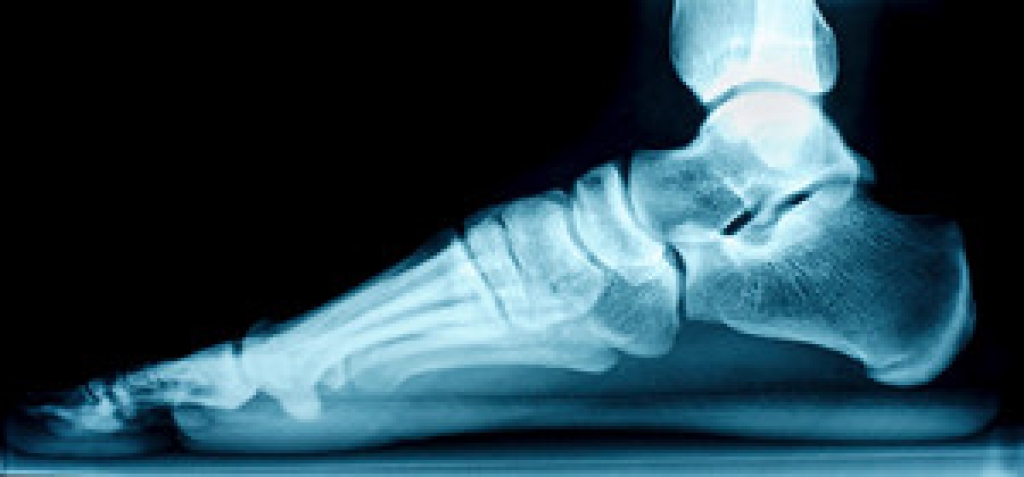

Pickleball, a popular sport combining elements of tennis, badminton, and table tennis, has gained a dedicated following in recent years. However, like any physical activity, it carries the risk of injuries, and one of the most common being plantar fasciitis. This is a painful condition characterized by inflammation of the plantar fascia, which is a thick band of tissue running along the bottom of the foot. The repetitive motions, quick lateral movements, and sudden stops and starts in pickleball can put immense strain on the plantar fascia. Over time, this strain can lead to tiny tears in the tissue, resulting in pain and discomfort, often most pronounced in the heel. Preventing plantar fasciitis in pickleball involves practicing proper warm-up routines, wearing appropriate footwear, and performing regular calf and Achilles tendon stretches. If injury strikes, resting and taking anti-inflammatory medications may help alleviate symptoms. Seeking professional guidance from a podiatrist is crucial for a tailored recovery plan, which may include exercises to strengthen the foot and improve biomechanics. By being proactive about injury prevention and prompt treatment, pickleball enthusiasts can continue enjoying this fun sport while minimizing the risk of plantar fasciitis and other common injuries. If you have heel pain from playing pickleball, it is suggested that you confer with a podiatrist who can offer you additional relief and treatment methods.

Foot and ankle injuries are a common occurrence when it comes to athletes of any sport. While many athletes dismiss the initial aches and pains, the truth is that ignoring potential foot and ankle injuries can lead to serious problems. As athletes continue to place pressure and strain the area further, a mild injury can turn into something as serious as a rupture and may lead to a permanent disability. There are many factors that contribute to sports related foot and ankle injuries, which include failure to warm up properly, not providing support or wearing bad footwear. Common injuries and conditions athletes face, including: